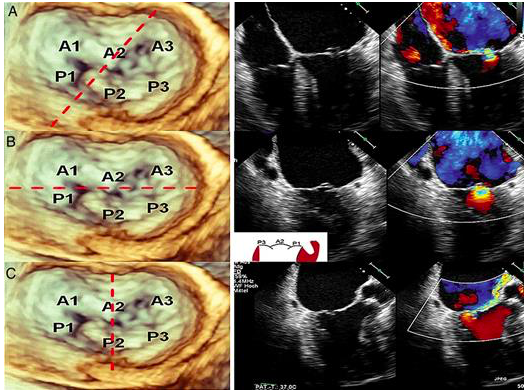

Basic investigations for mitral lesion

- Grade severity of MR

- Transthoracic echo

- Determine the morphology of mitral valve disease

- Transesophageal echo

- CT Thorax - Calcified aorta

- Coronary Catheterization - assessing MR jet, coronary anatomy if CABG is considered

ESC Tools

-

Determine the morphology of mitral valve disease

2013. European Heart Journal–Cardiovascular Imaging, 14(10), pp.935-949.

Ontario Mitral Valve Clip Procedure – Patient Eligibility Criteria Guidelines

Echocardiographic features that are favourable and unfavourable for MitraClip placement